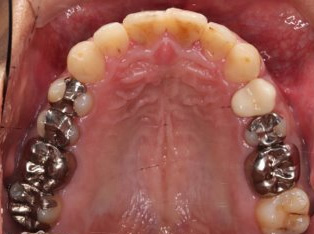

治療前

治療終了前